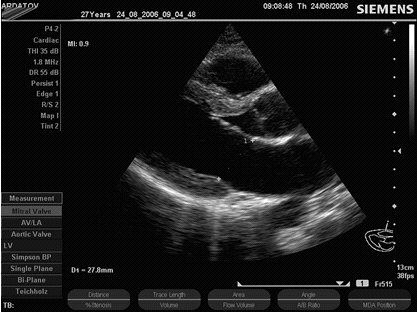

В заключение данного раздела привожу серию эхокардиограмм молодой женщины (27 лет), у которой выявлен комплекс МАРС, включающий косо-поперечную трабекулу в левом желудочке ближе к верхушке, увеличенную Евстахиеву заслонку, пролапс септальной створки трикуспидального клапана с регургитацией в правое предсердие I - II ст., незначимый пролапс передней створки (до 2-х мм) без регургитации, обусловленный, вероятно, увеличением ее длины (рис. 10, А - З ). Клинически имеют место жалобы на редкие колющие боли в области верхушки сердца в состоянии физического покоя, повышенная утомляемость (непостоянно), склонность к гипотонии, лабильность пульса со склонностью к тахикардии, повышенная "нервная возбудимость", астеническое телосложение, маловыраженная воронкообразная деформация грудной клетки, повышение подвижности в мелких суставах. Аускультативно тоны ясные, "нечистота систолы" слева по краю грудины в положении стоя, явные шумы не выслушиваются. ЭКГ - регулярный синусовый ритм 88 в мин., маловыраженные признаки синдрома ранней реполяризаци в грудных отведениях, вертикальное положение ЭОС.

Рис. 10. Незначимый пролапс передней створки МК в сочетании с другими МАРС (собственное наблюдение).